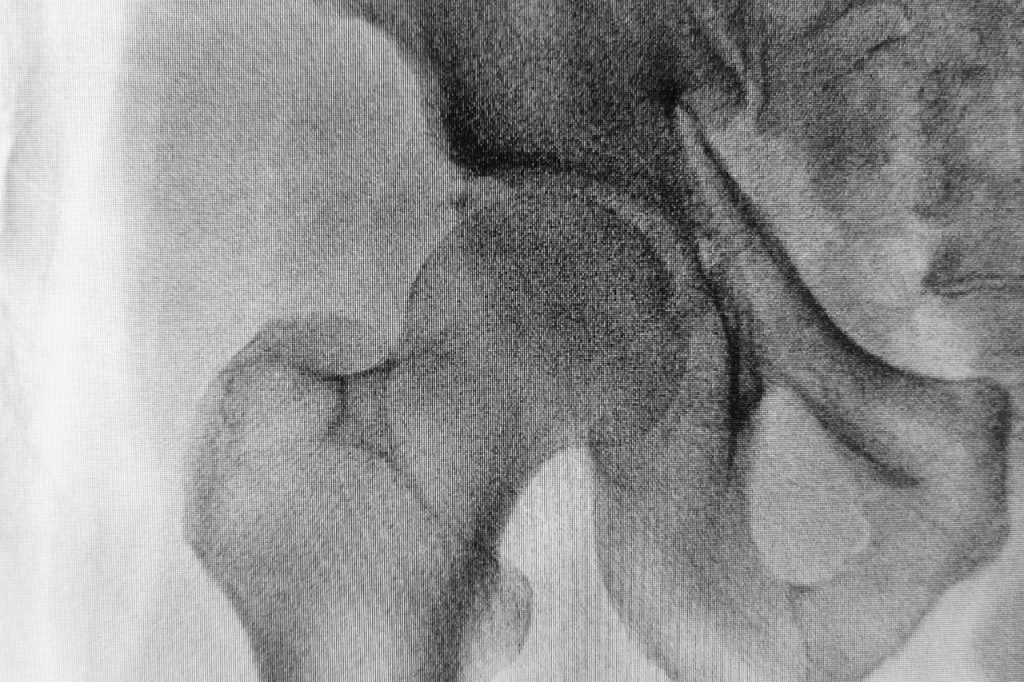

Panewka stawowa jest to struktura kostna, pokryta z zewnątrz tkanką chrzęstną. We wklęsłej powierzchni panewki mieści się, również pokryta chrząstką, główka innej kości. Do uszkodzenia panewek stawu biodrowego najczęściej dochodzi na skutek urazów, podczas których na staw działa duża siła. Tego typu kontuzje najczęściej dotykają osób ćwiczących wyczynowo, na przykład piłkarzy, biegaczy długodystansowych, gimnastyków itp. Do przeciążeń stawowych może dojść również w wyniku dźwigania nadmiernych ciężarów, nadwagi lub zmian zwyrodnieniowych spowodowanych nawarstwionymi przez lata mikrouszkodzeniami.

Czynnikami powodującymi uszkodzenia panewki mogą być wady postawy, niektóre przebyte choroby, wrodzona dysplazja stawu biodrowego, konflikt panewkowo-udowy, brak równowagi mięśni bioder i miednicy i błędy treningowe. Przyczyną uszkodzenia panewki stawu biodrowego mogą być urazy mechaniczne w wyniku wypadków komunikacyjnych lub upadku ze znacznej wysokości na bok ciała. Staw biodrowy pracuje w każdej pozycji, a więc częste przeciążenia mogą skutkować uszkodzeniem panewek stawu.

Uszkodzona panewka biodra skutkuje ograniczeniami ruchomości i wymaga specjalistycznego leczenia oraz rehabilitacji. Leczenie uzależnione jest od rodzaju i stopnia uszkodzenia panewki stawowej. W klinice ortopedii i medycyny sportowej Carolina Medical Center pacjenci diagnozowani są na podstawie wywiadu lekarskiego, badań klinicznych i diagnostyki odpowiedniej obrazowej. Zależnie od wyników badań stosuje się leczenie zachowawcze lub chirurgiczne. Leczenie zachowawcze polega na ograniczeniu aktywności fizycznej, wdrożeniu postępowania przeciwbólowego i przeciwzapalnego, a gdy minie ból wprowadza się ćwiczenia rehabilitacyjne trwające do 6 tygodni. W przypadkach braku oczekiwanych rezultatów pozostaje stosowny zabieg za pomocą technik artroskopowych lub operacji otwartej. Po okresie rekonwalescencji pacjenci podejmują rehabilitację trwającą 10-12 tygodni.